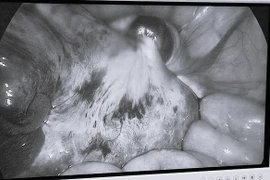

Các bác sĩ tại Bệnh viện Phụ sản TP. Cần Thơ đã phẫu thuật bóc tách thành công khối u nang buồng trứng có kích thước lớn cho sản phụ đang mang thai tuần thứ 16, đồng thời bảo đảm sức khỏe thai nhi ổn định.

Xoắn u buồng trứng là một trong những cấp cứu phụ khoa nguy hiểm, chiếm khoảng 2-3% các trường hợp cấp cứu khẩn cấp. Tình trạng này đặc biệt nghiêm trọng đối với phụ nữ mang thai, đe dọa sức khỏe cả mẹ và bé.

Đau bụng vùng hố chậu phải, kèm theo nôn ói, bệnh nhi được gia đình cho uống thuốc nhưng không cải thiện, đi khám phát hiện khối u buồng trứng trái bị xoắn hiếm gặp.